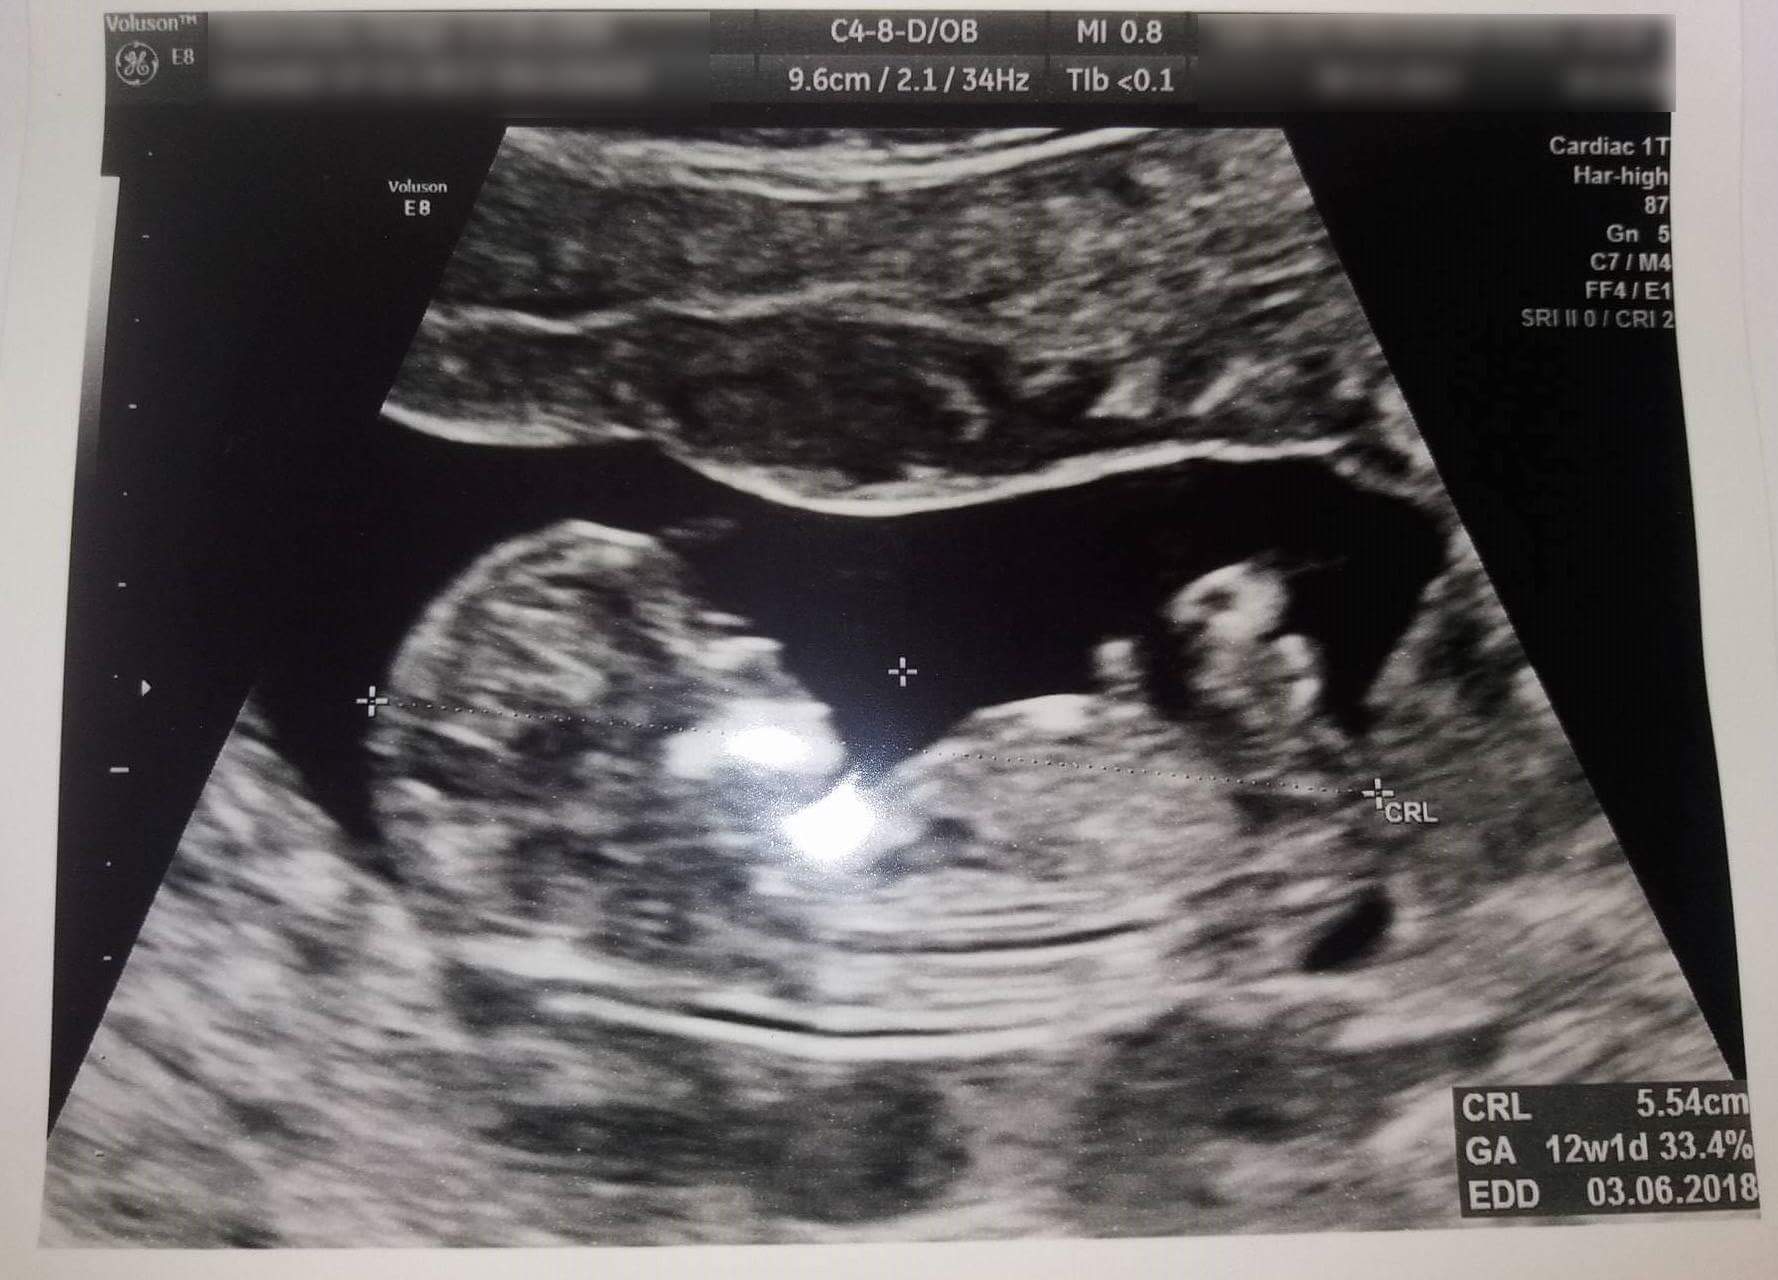

Ja miałam na NFZ genetyczne z pappa to zrobiłam. Generalnie w ciąży robię wszystkie badania jakie się powinno bo za dużo przeszłam i nie chcemy z lekarzem nic przeoczyć.